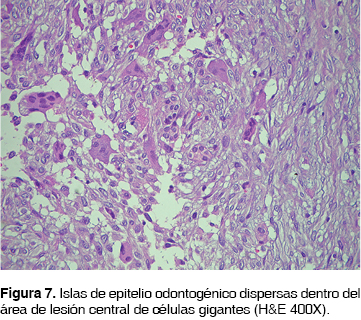

Microscópicamente el tumor estaba conformado por tejido fibrocelular bien vascularizado que formaba fascículos entrelazados de células fusiformes con escasa producción de colágeno, entre las que se observaron abundantes islas y cordones de epitelio odontogénico inactivo. En algunas zonas especialmente hacia la periferia de la lesión, se apreciaron áreas compuestas por tejido fibrocelular altamente vascularizado, en la que se identificaron numerosas células gigantes multinucleadas tipo osteoclasto, dispersas y distribuidas principalmente alrededor de los vasos y zonas de hemorragia intralesional (Figuras 6 y 7).

El caso aquí reportado se muestra histológicamente conformado por tejido fibrocelular bien vascularizado que forma fascículos entrelazados de células fusiformes con escasa producción de fibras colágenas, entre las que se observan abundantes islas y cordones de epitelio odontogénico inactivo. En algunas zonas, se aprecian áreas compuestas por tejido fibrocelular altamente vascularizado, en la que se identifican numerosas células gigantes multinucleadas tipo osteoclasto, dispersas y distribuidas principalmente alrededor de los vasos y zonas de hemorragia intralesional. Estos hallazgos son similares a los descritos en los casos previamente reportados, lo que apoya el concepto de que esta lesión es una entidad en sí misma.